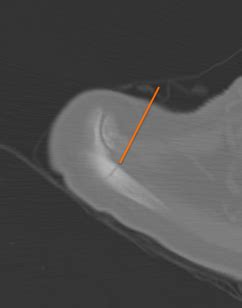

Radiographs showed a lesion at the neck of the glenoid with aggressive features.

A case report from injury, she was doing very well, without symptoms, and was participating in collegiate water polo. At 9 months scapular stress fracture in water polo: Your collarbone, arm bones, lungs, or chest may also be affected. A stress fracture is a small fracture in a bone. Stress fractures result from recurrent and repetitive loading of bone. The continuous scapular motion and recruitment of the scapular stabilizers to maintain buoyancy expose water polo athletes to the risk of scapular stress fracture. Massachusetts institute of technology cambridge, ma 02139. Stress fractures are tiny cracks in bones often caused by overuse or osteoporosis. Epidemiology associations scapular fractures are often associated with other injuries due to the high energy. A case report from injury, she was doing very well, without symptoms, and was participating in collegiate water polo. Scapular stress fracture initially masquerading as tumor or infection. Stress fractures can take weeks or months to heal. In runners, it typically happens in one of the legs. Instead of resulting from a single severe impact, stress fractures are the result of accumulated injury from repeated submaximal loading, such as running or jumping. Thankfully, stress fractures in the large bones of the body are rare. The angle of the bone causes a deformity in the limb (angular deformity)3. Scapula fractures are uncommon injuries, representing ~3% of all shoulder fractures.